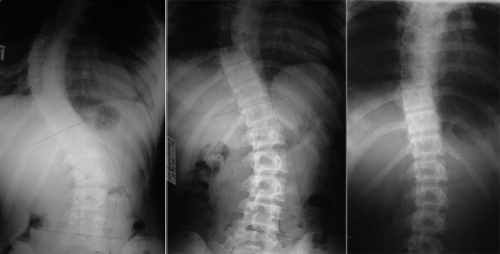

При S-образном сколиозе позвоночник принимает форму латинской буквы “S”, что и дало название этому состоянию. При анализе позвоночного столба в фронтальной проекции можно увидеть два изгиба: один в грудном отделе и другой — в поясничном.

S-образное искривление часто путают с Z-образным сколиозом, однако между ними есть важные различия. В первом случае наблюдаются два изгиба в разных отделах позвоночника, во втором — три. Механизм формирования двух изгибов прост: сначала возникает дефект в одном из отделов позвоночника, и для восстановления равновесия позвоночный столб создает искривление в другом отделе. Поэтому при S-образном сколиозе обычно затрагиваются грудной и верхний поясничный отделы.

Для оценки степени развития патологии проводится рентгенография. Снимки выполняются в двух проекциях, что связано с изменением положения позвонков. Также могут быть назначены МРТ и КТ. Рентгенография позволяет установить стадию сколиоза, но не дает информации о состоянии внутренних органов и мягких тканей. Для этого используются МРТ и КТ.